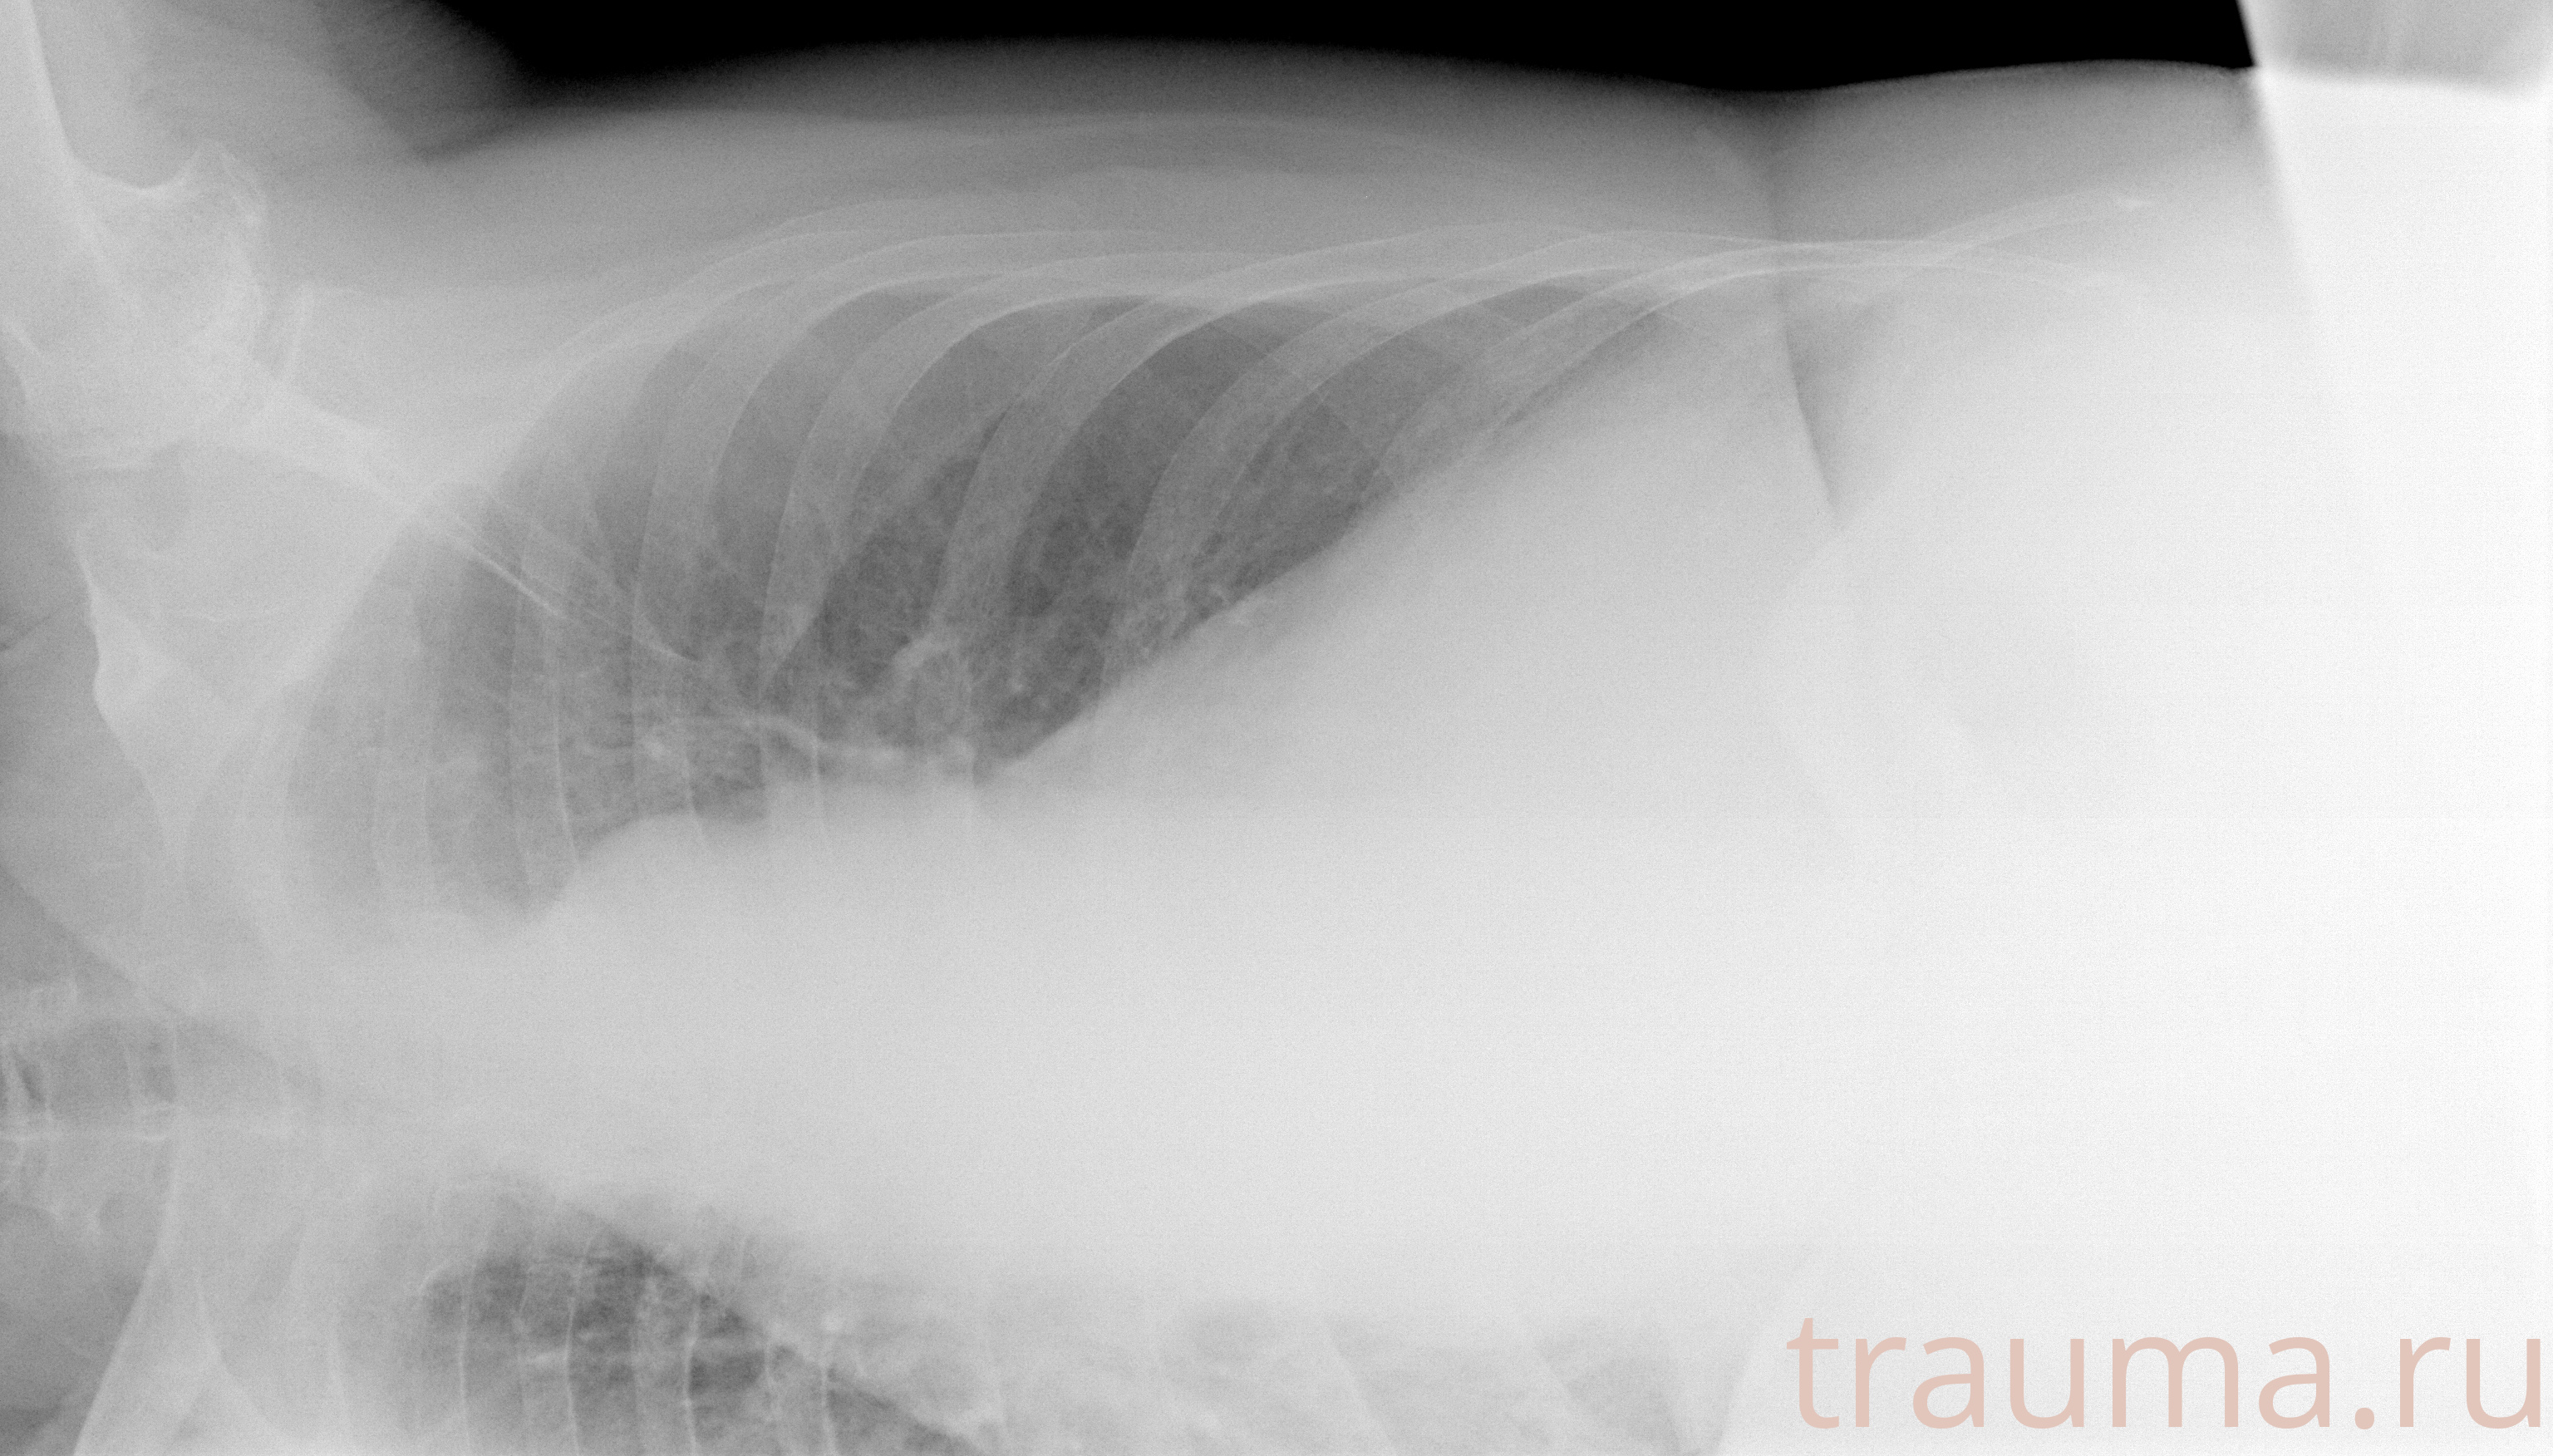

Рентген на дому: по вашему адресу приезжает врач-рентгенолог, травматолог-ортопед с мобильным рентгеновским аппаратом, проводит диагностику травмы или заболевания, делает необходимые рентгенограммы, дает рекомендации по дальнейшему лечению. Получить качественные снимки в домашних условиях возможно благодаря уникальной методике, разработанной МосРентген Центром для института  Склифосовского

при переломе шейки бедра и пневмонии от компании МосРентген Центр - партнера Института имени Склифосовского